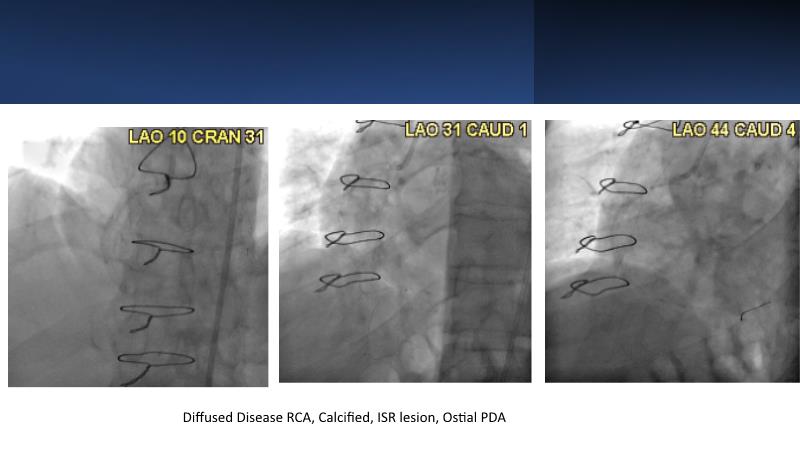

Next generation of DES technology, what it's all about? Find out in this session where experts will present complex cases from around the world and discuss the new indications for which they can be used.

• To know why and how a fusion coating of DES+DCB stent platform is effective for the treatment of cardiovascular disease in diabetes mellitus patients via case presentations

• To understand why you can count on customised drug delivery platform of DES+DCB in complex settings with imaging-based evidence through case presentations

• To gain an insight on how the next generation no-polymer DES+DCB stent platform will address the unmet needs in coronary artery disease patients